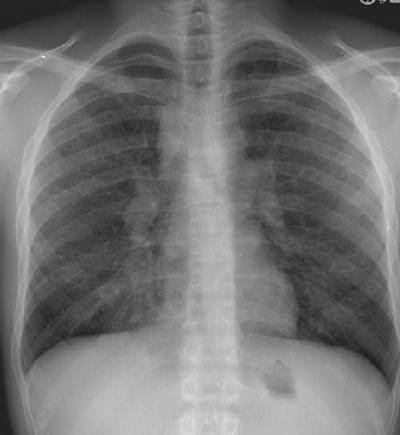

Sarkoidoz

Sarkoidoz nedir ?Birçok organlarda, ama özellikle akciğerlerde, dokularda kaba ve .  [ Devamını Oku ]